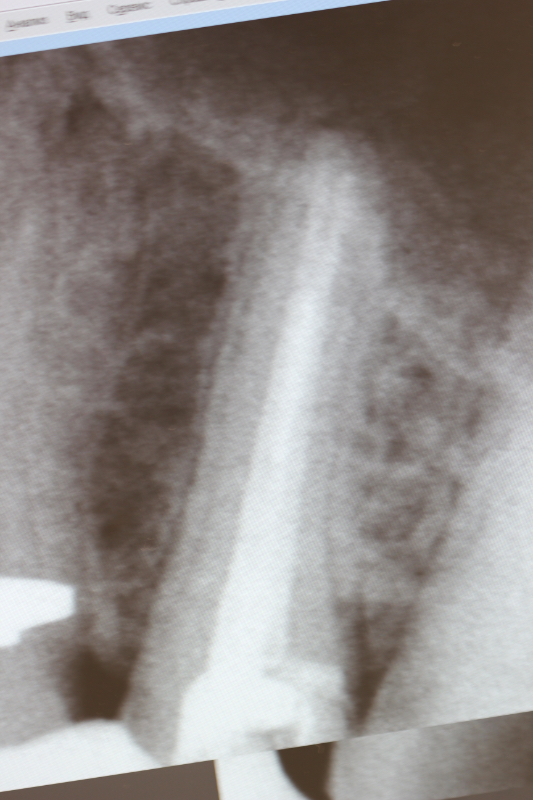

- Vyšetření a diagnostika — rentgen nebo CBCT, vysvětlení plánu léčby.